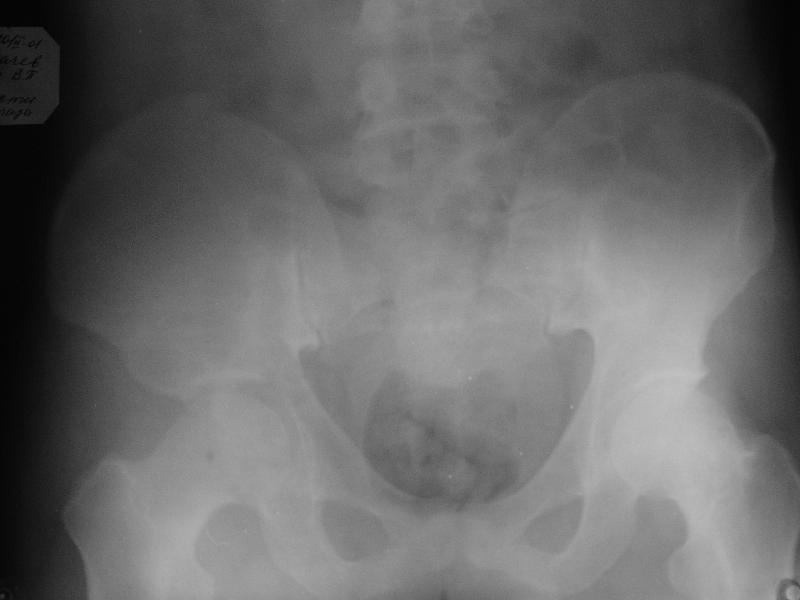

мужчина, 43 лет, получил травму в январе 2001 года. Лечился консервативно, в соседней области: скелетное вытяжение 6 недель, далее в кокситной гипсовой повязке 2 месяца. С декабря 2001 года ходит без дополнительной опоры, с компенсацией имеющегося укорочения - 4 сантиметра. С марта этого года беспокоят боли, усиливающиеся после умеренной физической нагрузки, возникающие в задних отделах таза и переходящие в область тазобедренного сустава. По данным ретгенографии и компьютерной томографии у больного имеется несросшийся высокий двухколонный перелом вертлужной впадины. Заранее спасибо.